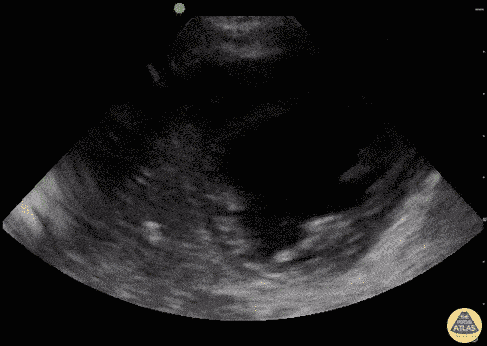

Pediatrics - Myocarditis (Infant)

1 y/o presenting with 1 day of respiratory distress with fever and coryzal symptoms. POCUS performed to assess lungs and heart. Infant found to have poor myocardial contractility on both parasternal long and short, despite use of dobutamine and milrinone drips. Also seen is a dilated left ventricle. BNP > 15,000 with highly elevated cardiac enzymes consistent with myocarditis. Dr. Sathya Subramaniam - Kings County/SUNY Downstate - Pediatric EM Fellow